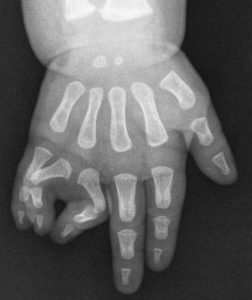

Fig. 2: Polidactilia Central

Polidactilia central (existência de dedo acessório a nível de D2, D3 ou D4)